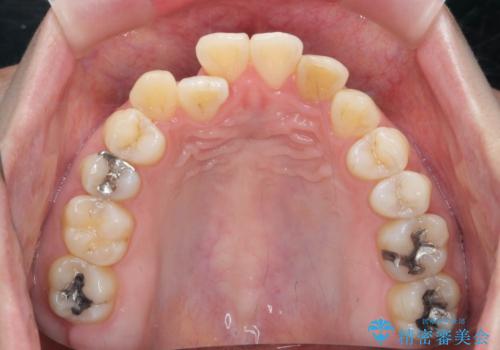

引っ込んだ前歯を並べたい マウスピースと部分ワイヤーのコンビネーション矯正

- 矯正装置

- インビザライン +部分ワイヤー矯正

- 引っ込んで生えてしまっている前歯を並べたい、と矯正治療を希望され来院されました。

まずマウスピース矯正インビザラインシステムで、引っ込んだ歯が並ぶためのスペースを作ったのち、部分ワイヤー矯正を行い短期間での配列を計画します。